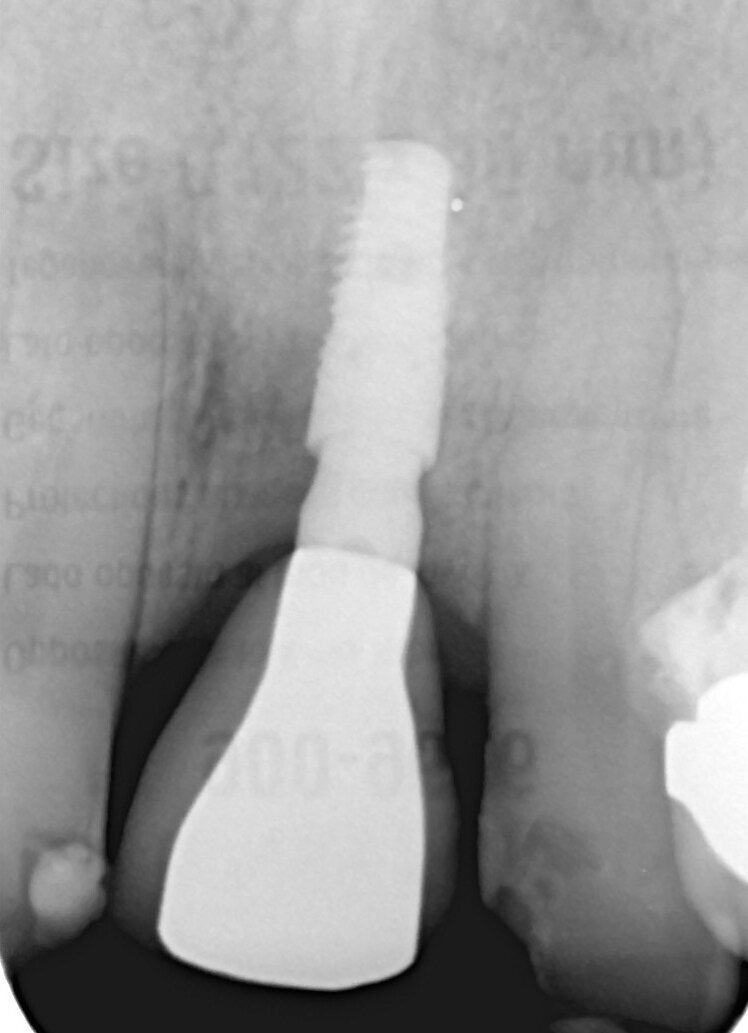

Fig. 6_Rx a 3 mesi con corona provvisoria.

Paziente di sesso maschile di 60 anni di età giunto alla nostra osservazione per una edentulia parziale dovuta all’assenza dell’elemento 1,1. La situazione clinica è resa esteticamente e funzionalmente complicata dalla assenza dell’elemento 2,2 che considerato lo spostamento dei denti contigui comporta un aumentato spazio per la sostituzione protesica dell’elemento 1.1. Si effettua dopo rx di controllo il posizionamento di un impianto osteintegrato GTB diametro 3,6 x 9 mm ,con posizionamento, come da protocollo, 1,5 mm sottocrestale ed inserzione immediata di moncone easy abutment slim 3,4 x 7 mm altezza gengivale 3,5 mm. angolato a 10 gradi (Easy Abutment Slim – GTB Plan1Health Amaro, UD, Italy). Con l’ausilio di una cappetta easy si costruisce e si cementa, con tecnica extraorale, una corona provvisoria in resina acrilica con forma a pontic su elemento 1.1 in modo da eseguire un carico immediato e fornire al paziente una estetica immediata (Figg. 1-3). Dopo 12 settimane ad avvenuta osteointegrazione si provvede all’impronta definitiva eseguita a livello abutment con elastomero di precisione Aquasyl Monophase (Dentsply) e con idonea cappetta easy (GTB Plan1Health Amaro, UD, Italy). La stessa cappetta easy viene utilizzata dal laboratorio odontotecnico come cappetta da sovrafusione garantendo standard di precisione stabiliti industrialmente (Figg. 4-8). La corona costruita in lega preziosa e porcellana viene cementata dopo una settimana, fatte le prove estetiche e occlusali necessarie sul paziente. I controlli a distanza di 4 anni, sia radiografici che clinici, confermano la stabilità dell’osso intorno all’impianto e la mancanza di perdita di tessuto gengivale attorno allo stesso (Figg. 9-11).